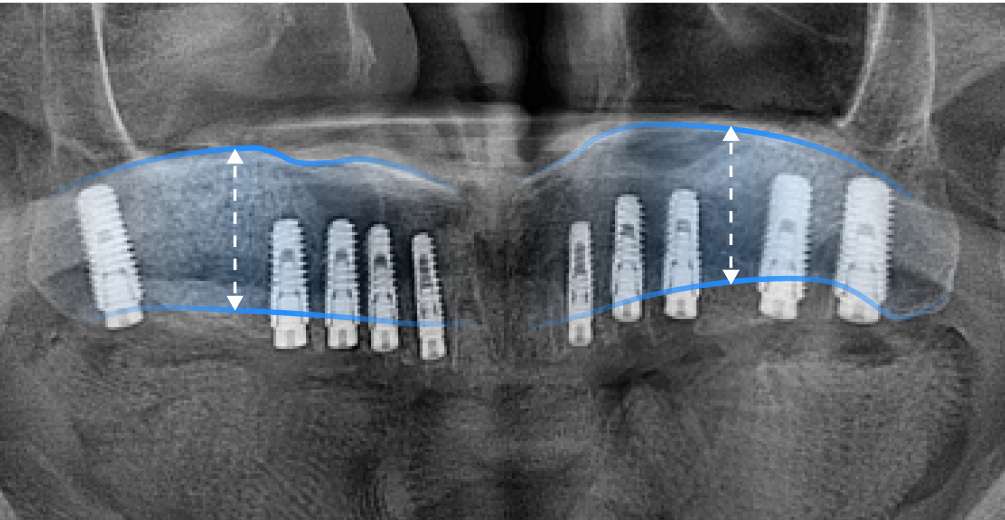

상악동은 원래 팽창하려는 성질이 있어 치아가 빠진 이후 오랜 시간 방치했거나 나이가 들면서 치조골이 약해지면 상악동이 아래로 내려오면서 커지는 증상이 발생합니다. 이를 상악동의 함기화(Sinus Pneumatization) 라고 하며, 상악동이 아래로 내려오면서 임플란트 식립이 어려울 만큼 뼈가 얇아지게 됩니다. 이렇게 뼈가 얇아져 임플란트 식립이 어려울 때, 상악동을 위로 들어 올려 뼈를 이식하는 ‘상악동 거상술(Sinus Lift , Sinus Elevation)’을 진행합니다.

• 상악동 거상술 전

상악동 거상술 전, 얇은 잇몸뼈

• 상악동 거상술 후

상악동 거상술 후, 두꺼워진 잇몸뼈

*노란선 : 잇몸뼈와 상악동의 경계선 *파란선 : 상악동 거상술 이후 잇몸뼈와 상악동의 경계선